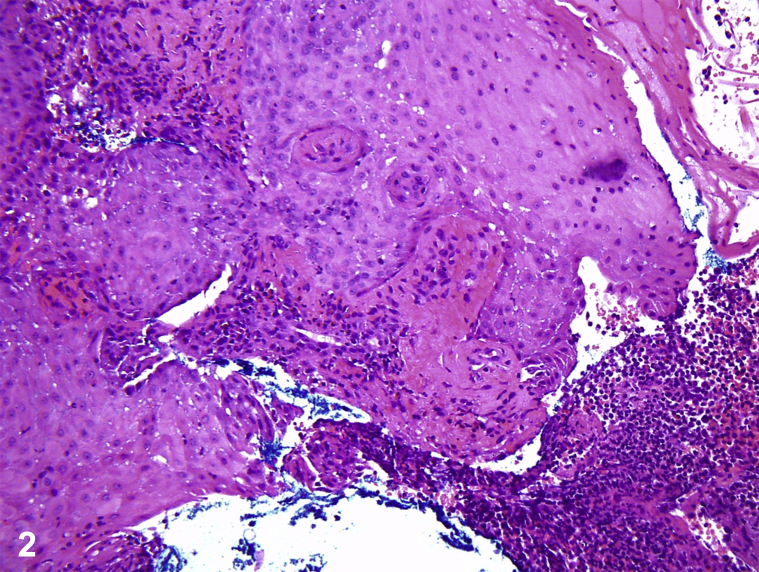

A teenage boy with Crohn's disease, treated with 6-mercaptopurine (6-MP) and mesalamine, had tender, hemorrhagic, vesiculobullous plaques on the hands, metacarpophalangeal joints, tongue, and face, which began as small red bumps (Fig 1). He was febrile to 38.7°C, pancytopenic, and neutropenic, with elevated erythrocyte sedimentation rate and C-reactive protein. Lesional pathology findings showed a neutrophilic infiltrate with occasional histiocytes but negative acid-fast bacilli and fungal stains (Fig 2). Lesional tissue culture revealed only methicillin-sensitive Staphylococcus aureus. Blood cultures were negative for bacteria and fungi. Positron emission tomography/computed tomography found axillary and mesenteric lymphadenopathy, deemed reactive. Bone marrow evaluation found hypocellular marrow, consistent with 6-MP toxicity, without malignancy.

Fig 2.